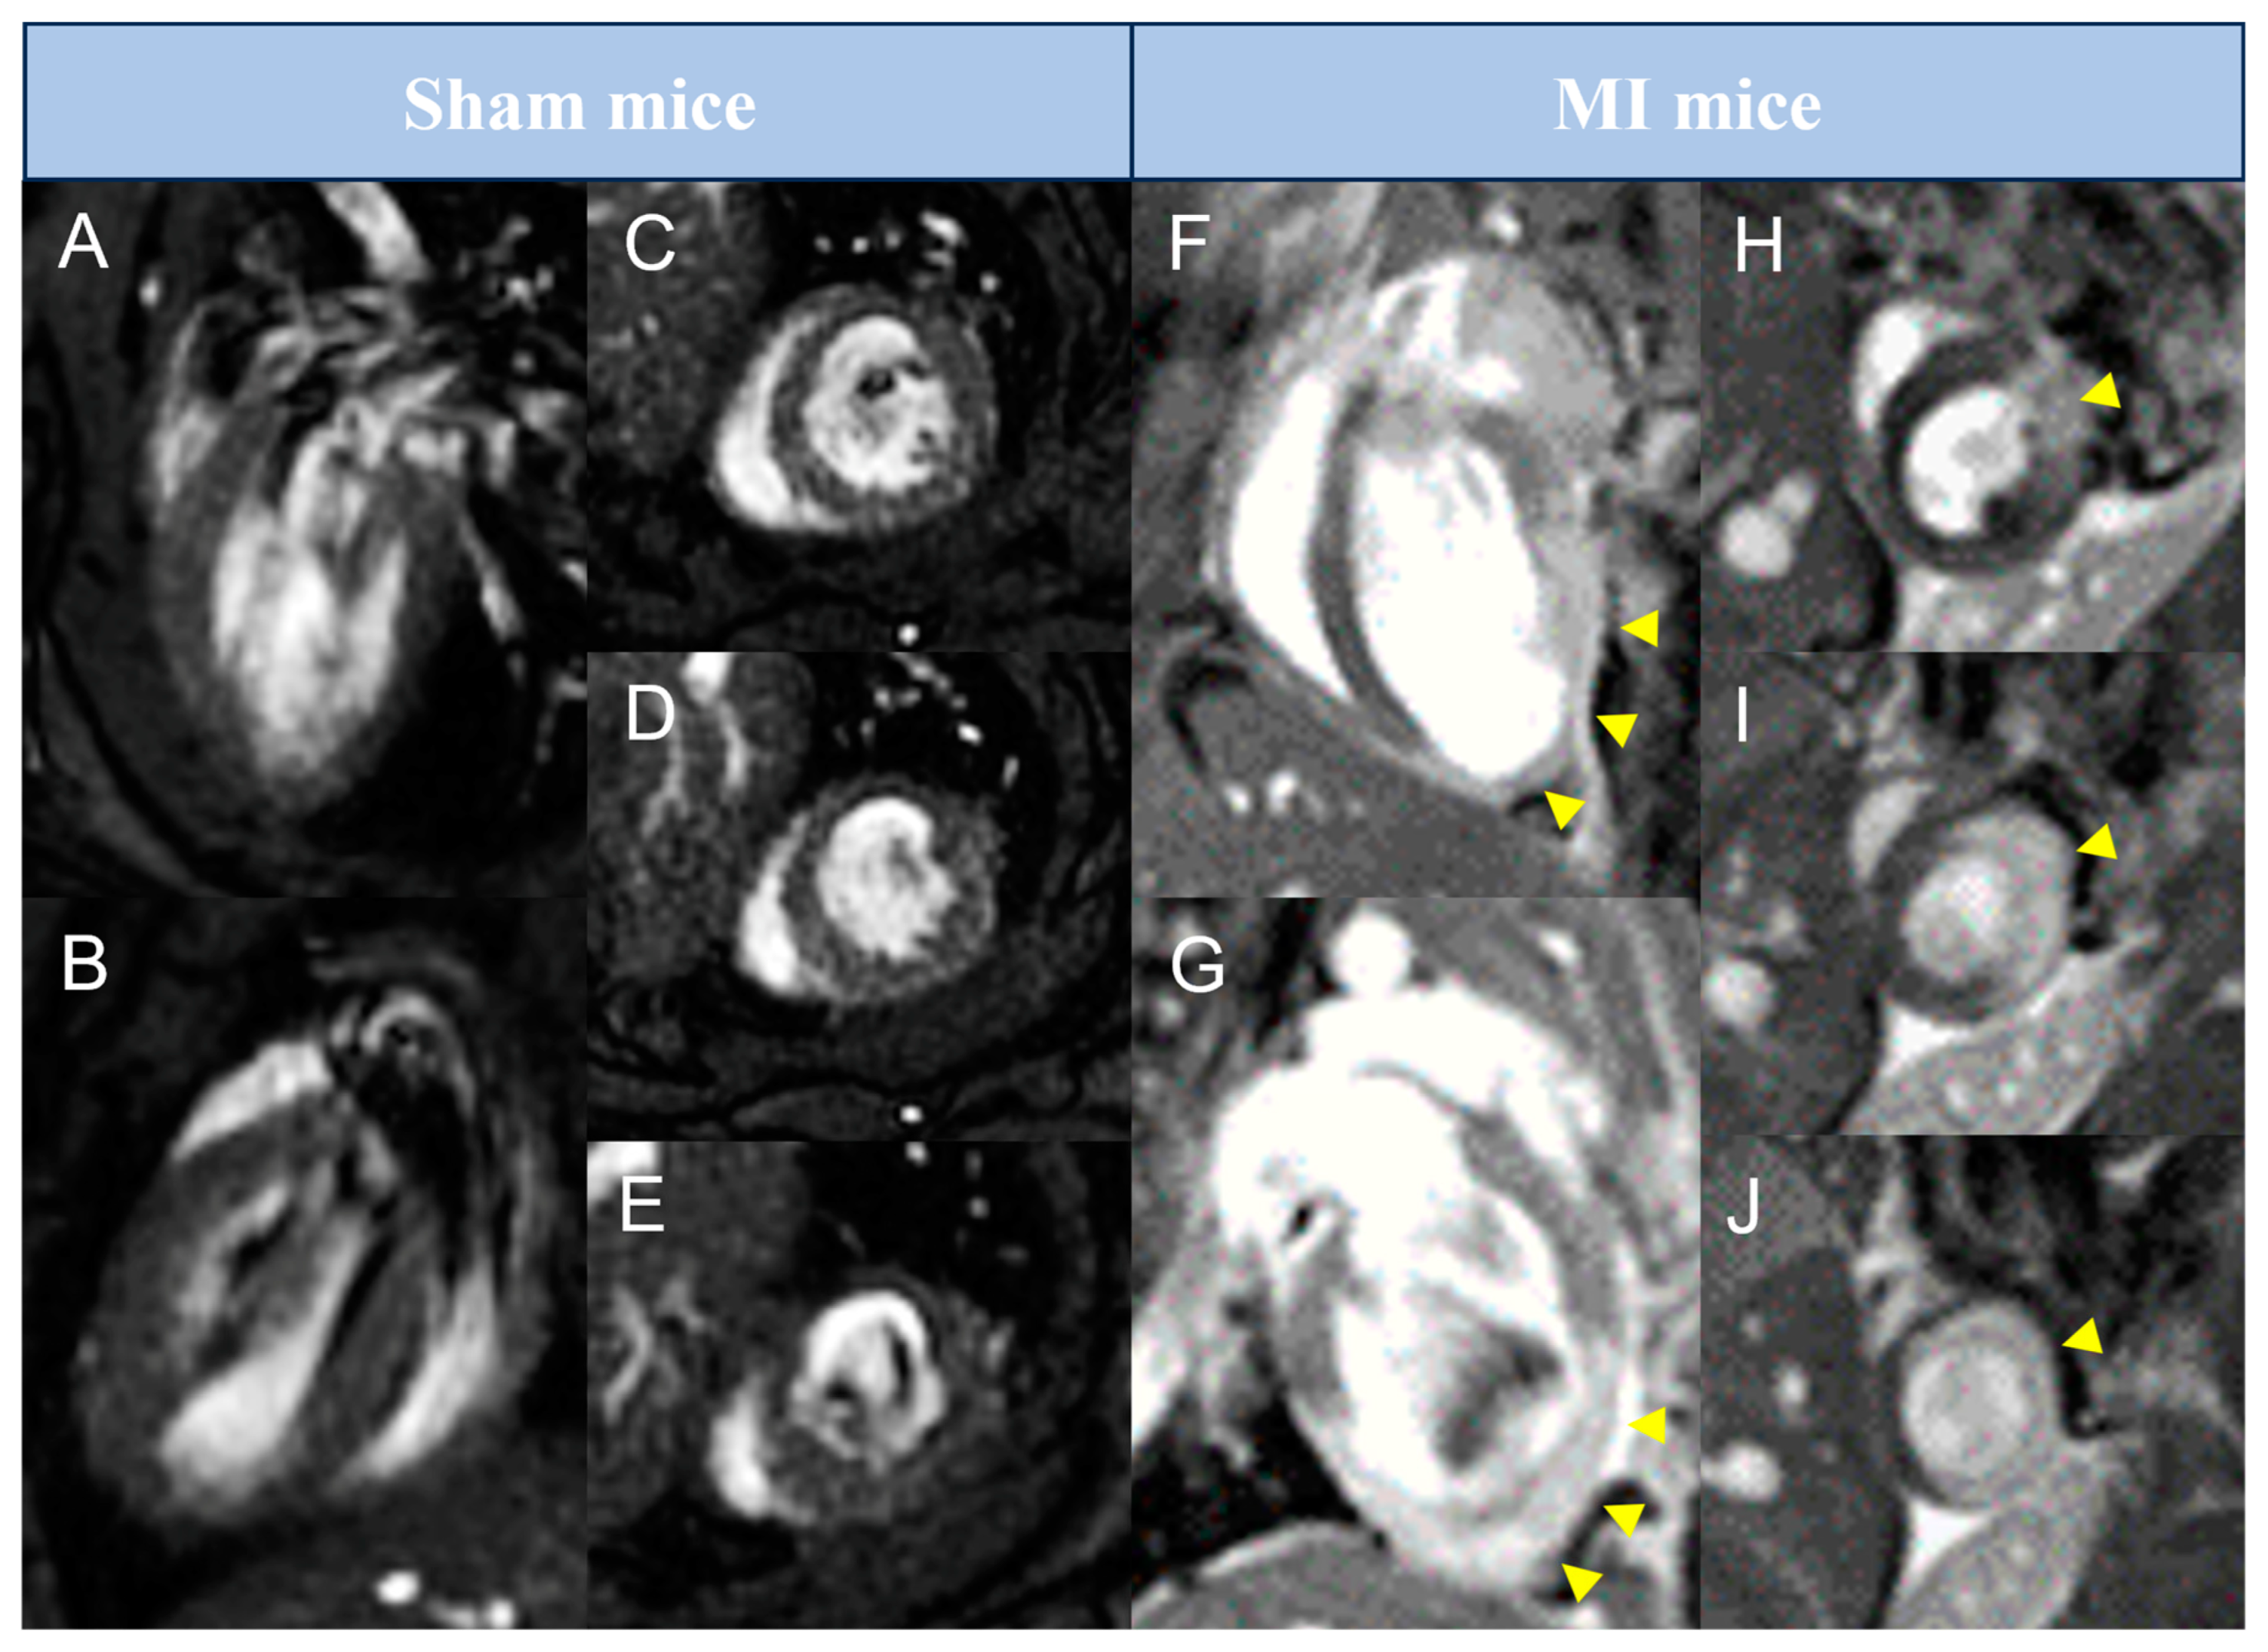

Mice in the two MI groups and sham controls underwent sequential CMR and PET imaging at baseline and at 1, 7, and 21 days after MI induction. Representative long-axis and short-axis CMR images from control, reperfused, and non-reperfused animals at day 21 are presented in Figure 1.

Figure 1. Representative pictures of late gadolinium enhancement–cardiovascular magnetic resonance studies performed in preclinical mice models. Animals from sham (AE) or MI (FJ) groups were submitted to cardiovascular magnetic resonance imaging 21 days after surgery. Representative pictures in long-axis (A,B,F,G) and in basal to apical short-axis (CE,HJ) are shown. Arrowheads represent areas with late gadolinium enhancement. MI = Myocardial infarction.